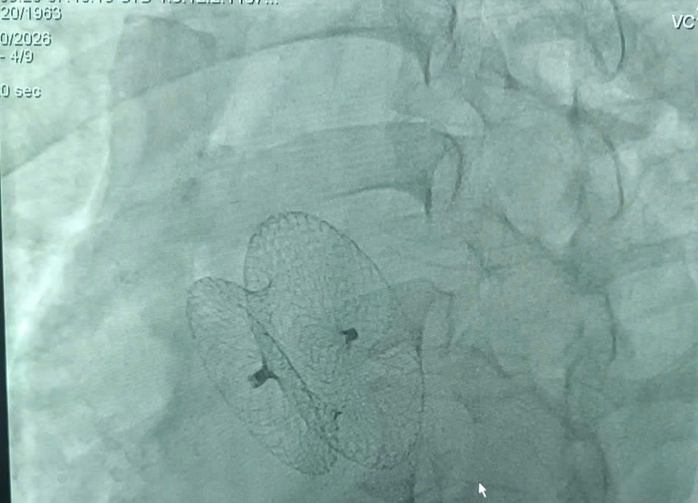

Bệnh nhân mắc thông liên nhĩ - một dị tật tim bẩm sinh. Ảnh: Bác sĩ cung cấp.

Bệnh nhân được can thiệp bít lỗ thông liên nhĩ